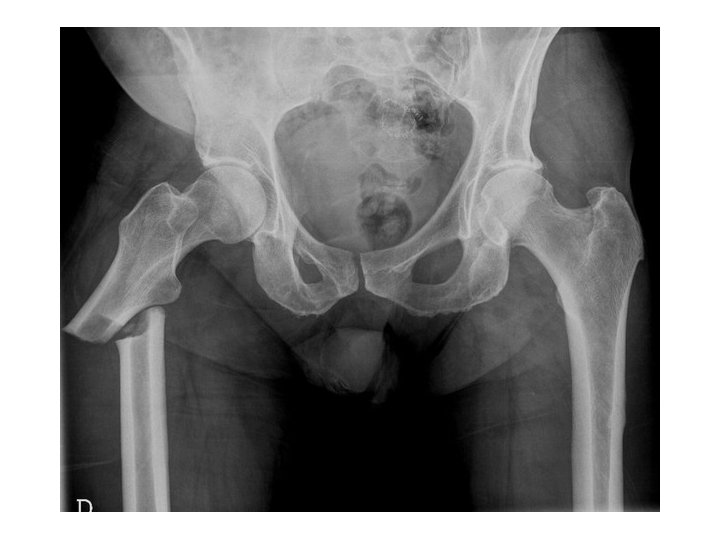

BAYONETTE APPOSITION

DISLOCATION

DISLOCATION • Note the dislocation on the previous slide; the articular surfaces of the knee no longer maintain their normal relationship • Dislocations are named by the positioin of the distal segemnt • This is an Anterior knee dislocation